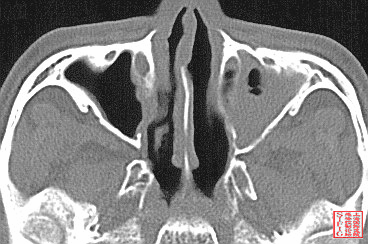

1990年RCT研究显示,鼻窦炎发生率,经鼻插管者(43.1%)显著高于经口插管(1.8%)。

Salord F et al. Nosocomial maxillary sinusitis during mechanical ventilation: a prospective comparison of orotracheal versus the nasotracheal route for intubation. Intensive Care Med. 1990;16(6):390-3.

Prospective RCT of 111 pts, randomized to either orotracheal or nasotracheal intubation; All had a nasogastric feeding tube. Primary outcome:  incidence of maxillary sinusitis by radiography (Waters' view) at the bedside. Maxillary sinusitis occurred in 1/53 (1.8%) of the orotracheal group (on the nasogastric tube side), and in 25/58 (43.1%) of the nasotracheal group (7 on the nasogastric tube side, 11 on the endotracheal tube side, 7 bilateral; p less than 0.001). long-term orotracheal intubation reduced significantly the incidence of maxillary sinusitis in comparison with nasotracheal intubation.

后有文章显示VAP发病率经口插管(6%,9/51)低于经鼻插管(11%,17/149),但这篇文章统计学没有显著意义 VAP发病率RR= 0.52 (0.24, 1.13)。后来我记得看到过另一篇RCT,说是有显著差异。